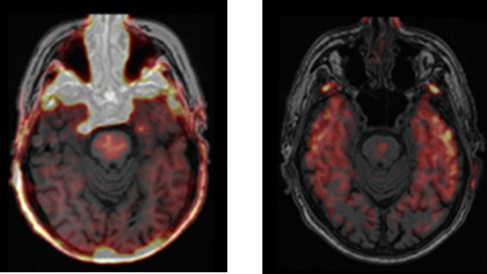

PET/MR brain scans in a person with Parkinson’s disease, using the tracer [11C]PK11195 as a marker of neuroinflammation (left image), and [18F]AV1451 as a marker of tau accumulation (right image)